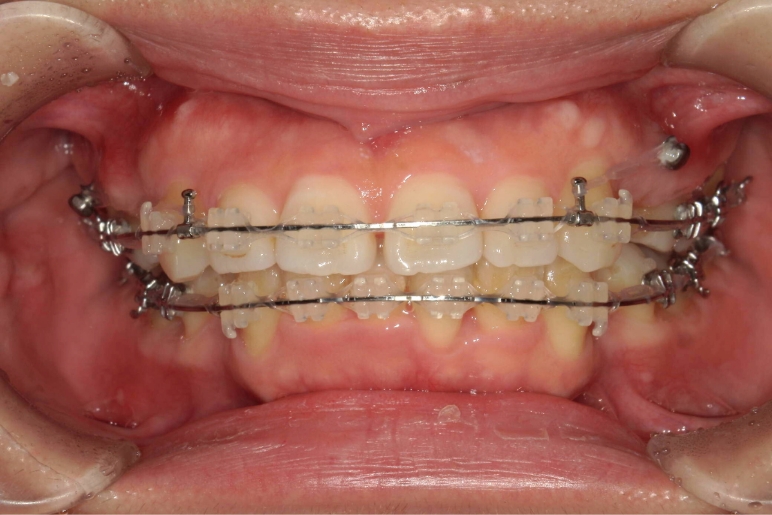

症例1:

出っ歯(上顎前突)を改善してガミースマイルも改善された症例

主訴 出っ歯、ガタガタ、ガミースマイルが気になる

診断名 上顎前突

初診時年齢 22歳

装置名 ワイヤー矯正、矯正用アンカースクリュー2本

抜歯部位 上顎右側第一小臼歯、上顎左側第二小臼歯、下顎左右第一小臼歯

治療期間 2年

費用 ¥910,000(税込¥1,001,000)

リスク・副作用 痛み、歯根吸収、歯肉退縮、虫歯、後戻り

治療のポイント 上顎前突でガミースマイルの場合、抜歯して、第二小臼歯と第一大臼歯の間にアンカースクリューを使用し、後上方に圧下しながら歯を下げることで、上唇が閉じやすくなるので歯茎が見えづらくなります。

Before

After